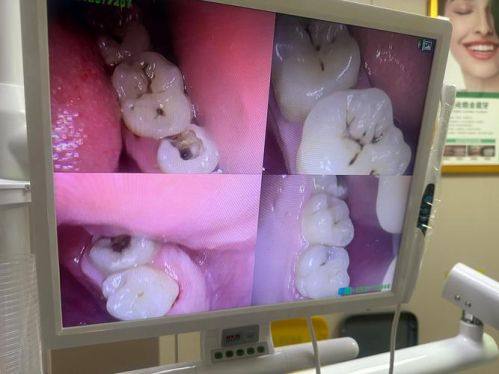

口腔保健:提供专精的口腔检查、清洁、口腔健康指导等服务,帮助患者及时发现口腔问题,养成良好的口腔护理习惯,有效预防各类口腔疾病的发生。

“我平时就特别注重口腔健康,定期会做口腔检查和清洁。北京芒果口腔的口腔保健服务做得特别专精,医生给我做了全方面的口腔检查,还耐心给我讲解了正确的刷牙方法和口腔护理要点。洗牙过程中医生手法轻柔,没有不适感,洗完后牙齿特别清爽。这里的环境也特别舒适,服务人员态度亲切,每次来都感觉特别放松,以后还会继续来这里做口腔保健。”